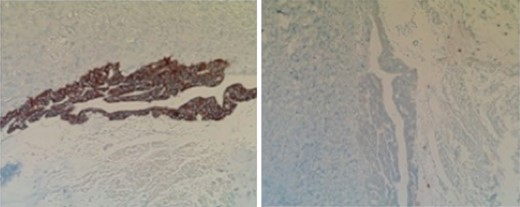

Subsequent surgical pathology results confirmed two separate malignant processes causing the carcinomatosis: Immunohistochemical examination was performed on the surgical specimens. The appendiceal tumor stained negative for CK-7 and positive for CK-20 (Fig. 1), whereas the ovarian sample stained positive for CK-7 and negative for CK-20 (Fig. 2), consistent with malignant processes of independent origins.

Left perforated ovarian mucinous adenocarcinoma with widespread involvement of fallopian tube and subserosa of sigmoid colon (carcinomatosis).